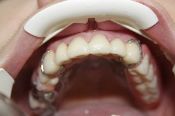

PARA AVALİAR O SEU PROBLEMA E TRAÇAR UM PLANO DE TRATAMENTO, BASTA ENVİAR-NOS FOTOS DA SUA BOCA E UM RAİO-X PANORÂMİCO. ENVİAREMOS GRATUİTAMENTE O RESULTADO DA AVALİAÇÃO DOS NOSSOS MÉDİCOS E TRAÇAREMOS UM PLANO DE TRATAMENTO.

1.

TIRE FOTOS DO MAXILA SUPERIOR

2.

FOTOGRAFIE A MANDÍBULA INFERIOR